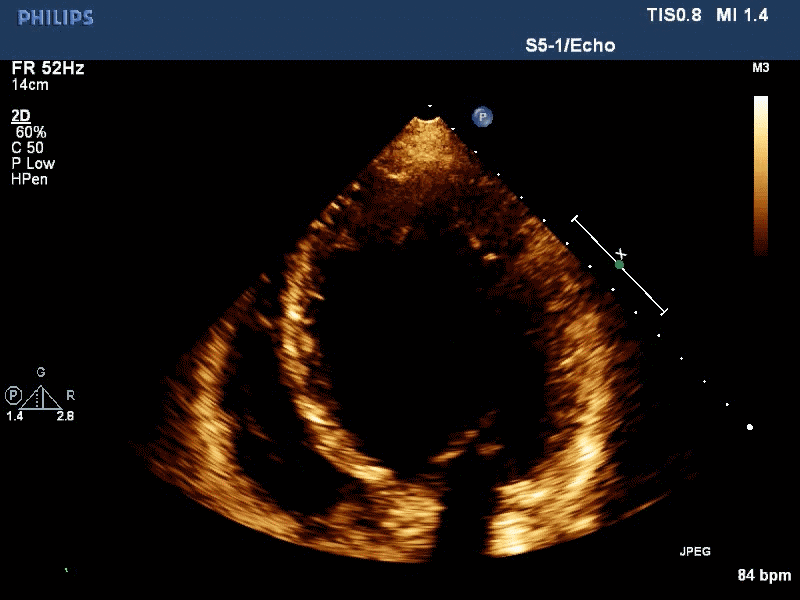

视频 显示左房内瘤体随心动周期的活动

左心房巨大粘液瘤,随心动周期往返于二尖瓣口 三

食管癌右室及肺动脉多处转移 左心房巨大粘液瘤,随心动周期往返于